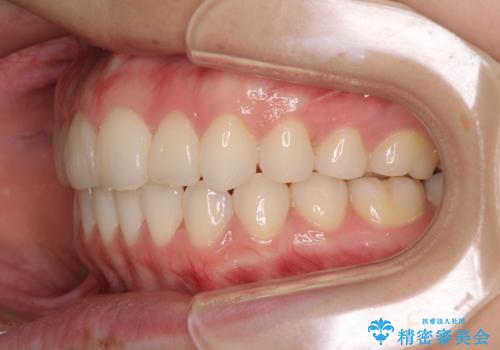

デコボコで飛び出した前歯をきれいに インビザラインによる矯正治療

- デコボコと飛び出した前歯を治したいとのことで来院された患者様です。

ゴムかけを活用して上顎歯列全体を後方移動し、IPR(歯と歯の間を削る)によってデコボコが解消するように設計し、インビザラインにより治療を行うこととしました。

毎日しっかりと装着してくださったので、概ねシミュレーション通りに歯を移動させることができました。

治療前には接触することのなかった上下の前歯が接触するようになり、食事の際前歯でものをかみ切れるようになりました。

気にしていた口元の印象が改善され、患者様には大変満足していただきました。